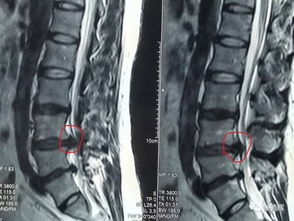

1、巨大型的椎间盘突出。

2、椎间盘突出后髓核脱垂到椎管。